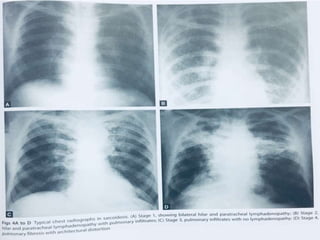

• 23.